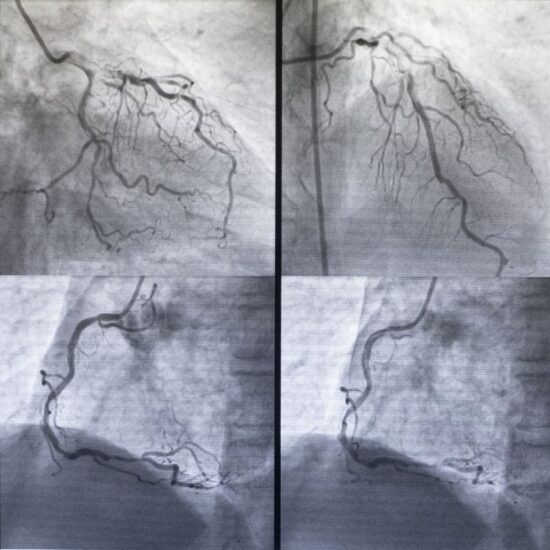

- Kalp kateterizasyonu: Bu test sıklıkla aort kapak hastalığını teşhis etmek için kullanılmaz. Ancak aort kapak hastalığının ne kadar şiddetli olduğunu görmek veya diğer testler başarısız olursa durumu teşhis etmek için yapılabilir. Bu testte doktor ince, esnek bir tüpü genellikle kasık bölgesinde veya kolda bulunan bir kan damarına yerleştirir ve bunu kalbe yönlendirir. Kalp arterlerinin tıkanmadığından emin olmak için aort kapak ameliyatından önce kalp kateterizasyonu da kullanılabilir.